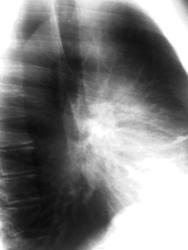

Непосредственно сама история: Пациент С. 35 лет. не курит. В детстве часто болел простудными заболеваниями. Обратился к участковому терапевту с жалобами на появившуюся одышку, общую выраженную слабость, "отсутствие сил". Направлен на флюрографию: был поставлен ошибочный диагноз "двусторонняя нижнедолевая пневмония". Назначен ударный курс антибиотиков. Облегчения никакого, у больного апатия, и навязчивая идея что он болен туберкулезом. Флюрография повторнопосле лечения, которую как раз мне и довелось описывать. Очень зацепил легочной рисунок!

в рекомендациях написал КТ-исследование ОГК. В виду интересности случая попросил участкового терапевта взять  ситуацию на контроль, чтоб пациент "не пропал". Больному дали талон на КТ, но каким то чудом Начмед больницы узнал, что из поликлиники больного прямиком направляют на КТ минуя классическую рентгенографию... Основываясь на своих доводах администратора и усмехнувшись (в прямом смысле слова) когда читал написаный мной дифференциальный ряд, заставил сделать обзурную рентгенограмму

ОГК в прямой и боковой проекции, результат тот же что и на флюшке: